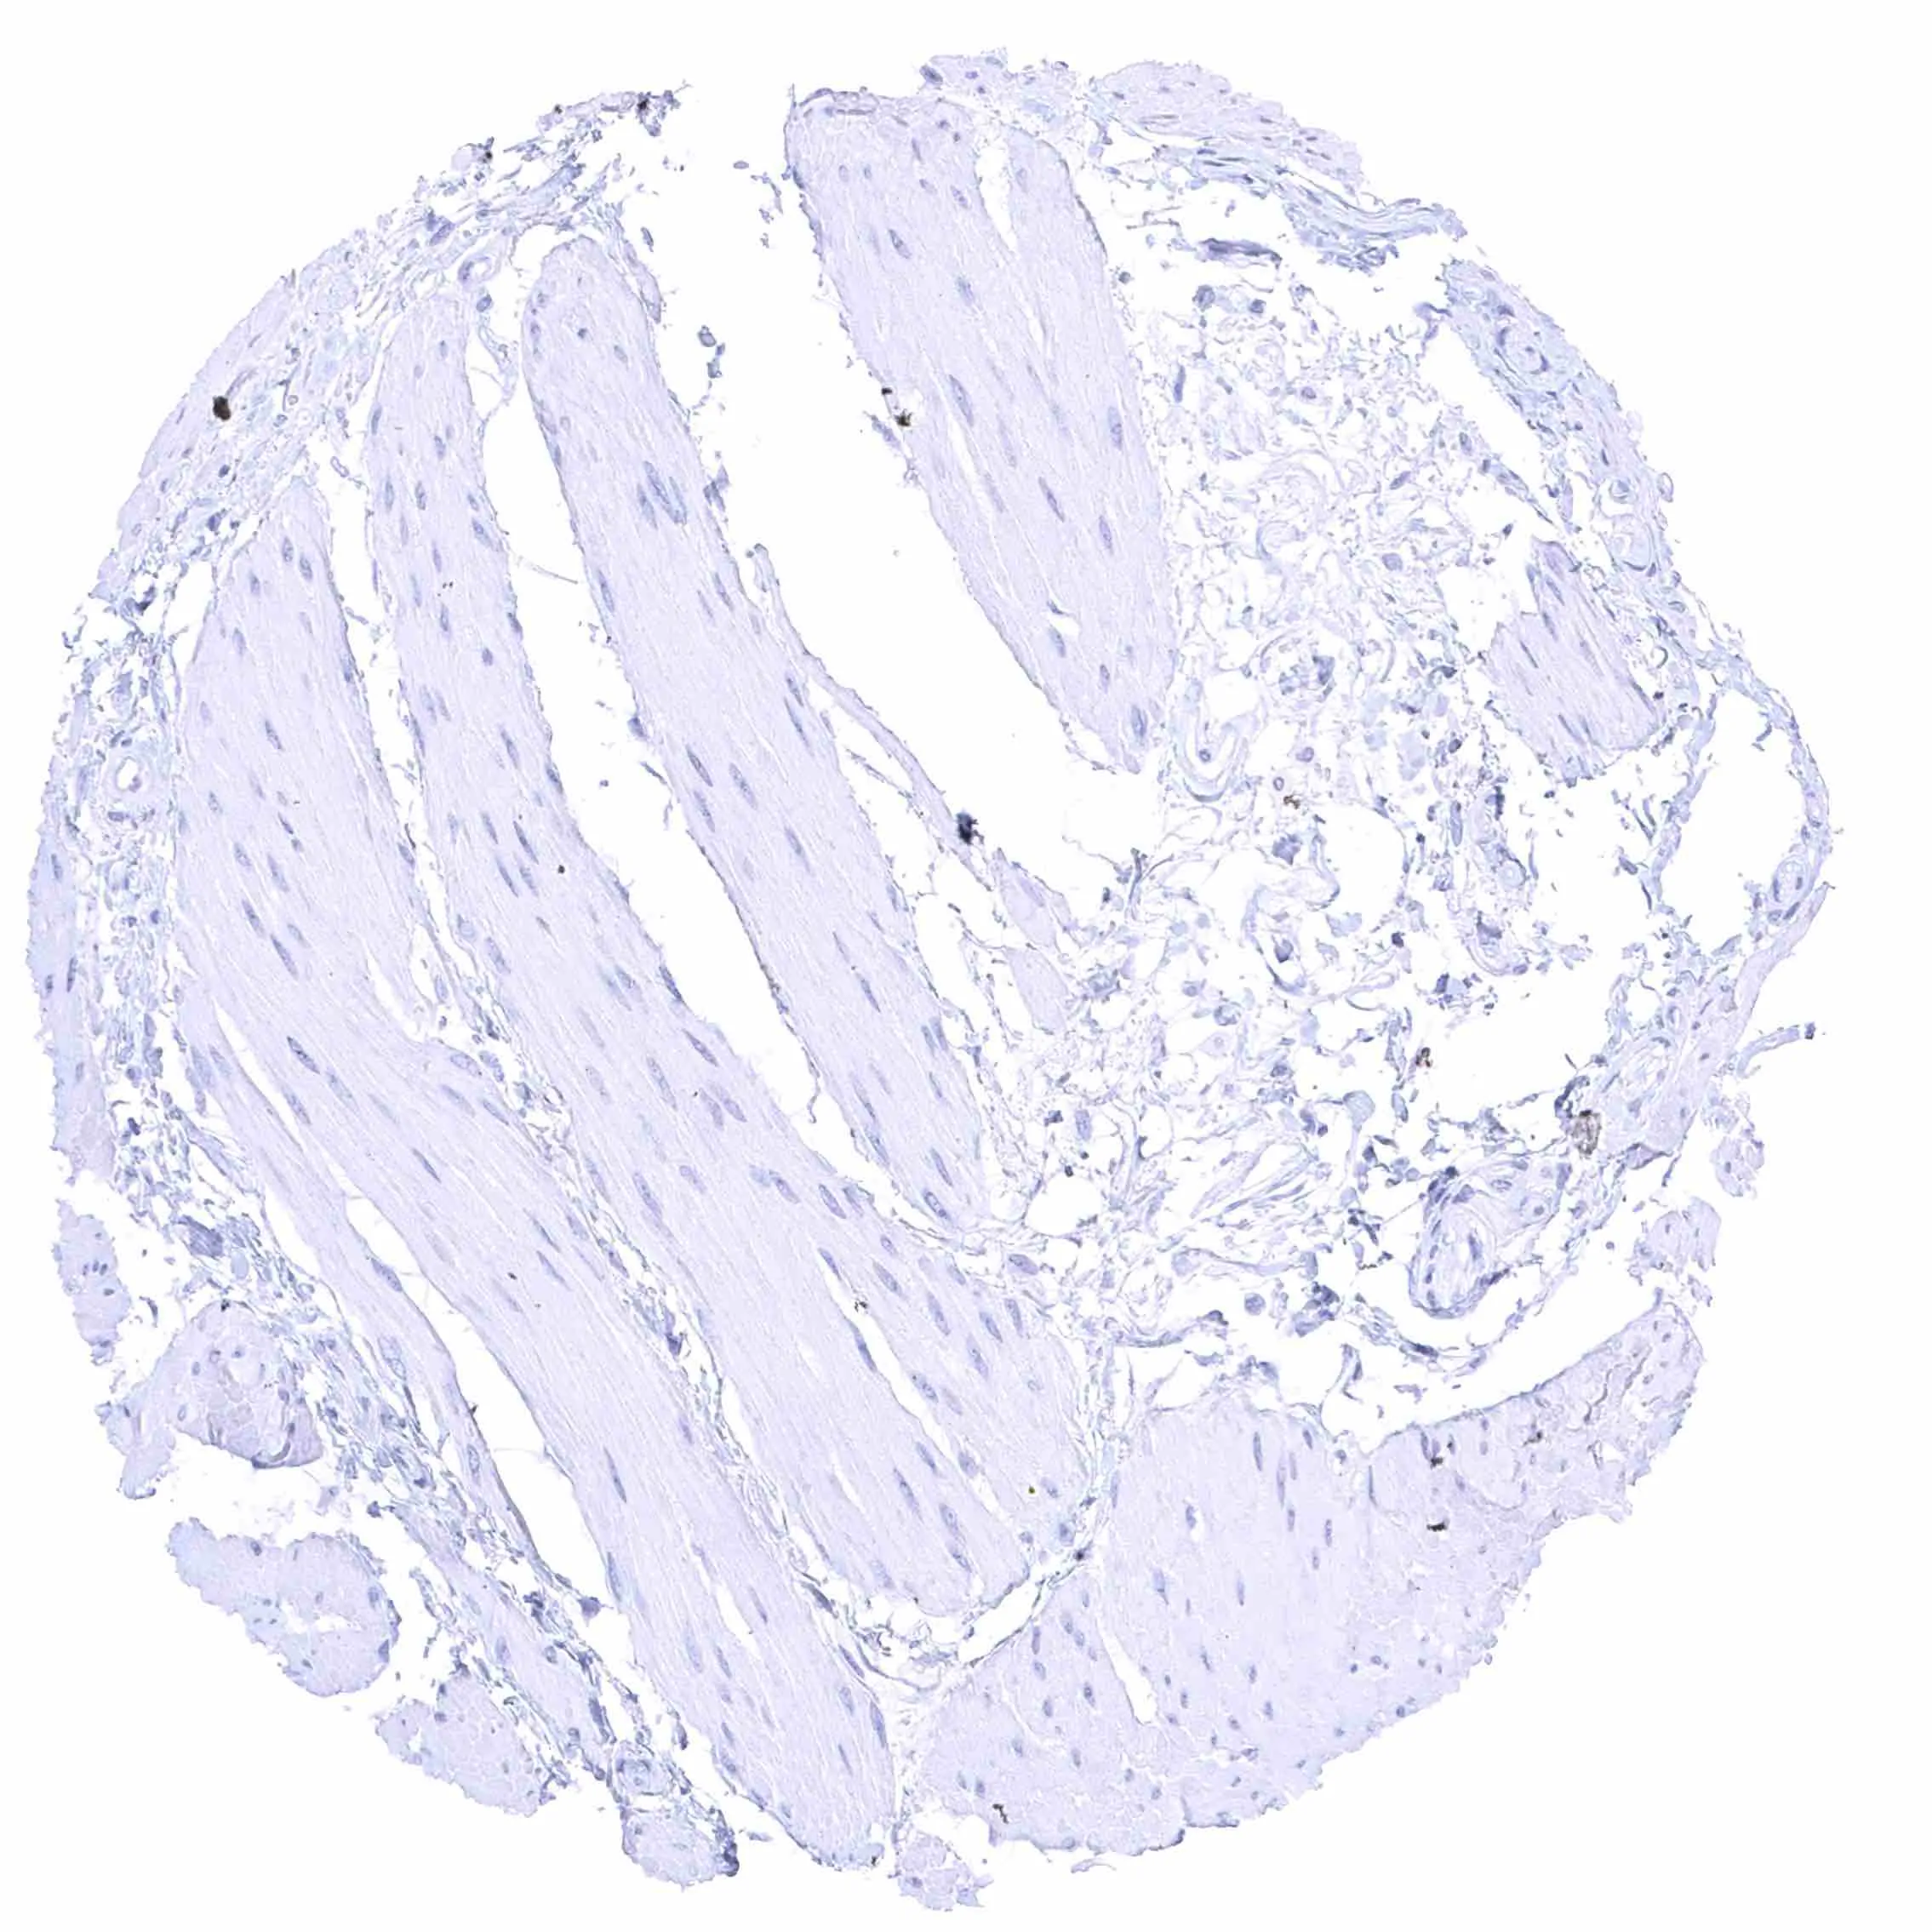

Skeletal muscle